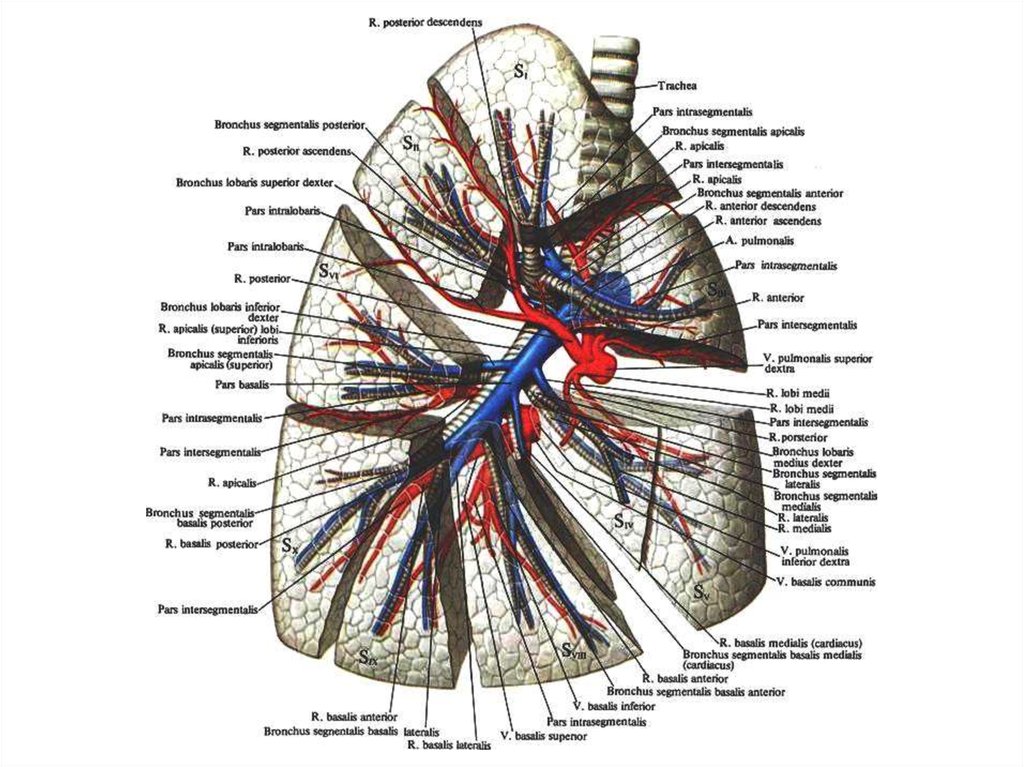

Анатомические изображения сегментов легких различных животных

Раздел: Другие животные